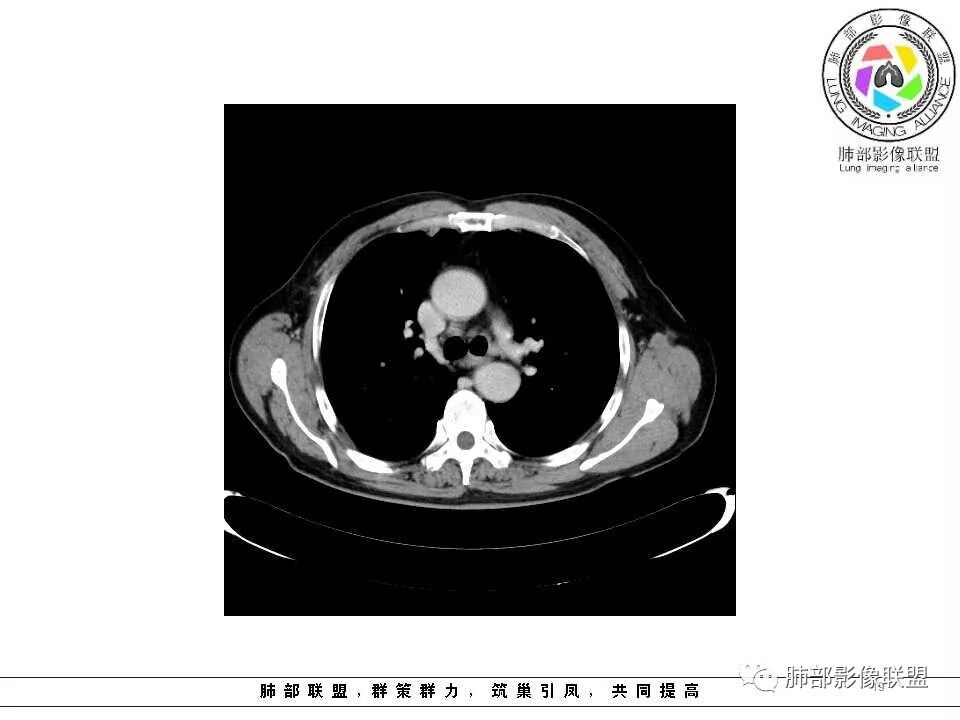

肺气肿背景,2016年左肺上叶上舌段见微结节,2017年5月左肺结节增大,密度均匀,边缘光滑锐利,与邻近血管关系密切,血管贴壁走行,外侧见尖状突起,下舌段片状影,沿着支气管走行,内有粘液栓,考虑鳞癌,鉴别小细胞肺癌。

肺气肿背景,2016年左肺上叶上舌段见微结节,一年后左肺结节增大,密度均匀,边缘光滑、膨隆,似见小分叶,下舌段片状影,沿着支气管走行,内,老年患者,咯血1月。考虑恶性病变并阻塞性肺炎,鳞癌?注意鉴别结核。

左肺上叶舌段支气管管壁略增厚 间隔一年 管壁增厚明显 向腔外突出形成结节 管腔闭塞 远端片状及斑片影 纵隔淋巴结增大 肺气肿背景 考虑鳞癌伴阻塞性炎症可能

老年男性,咯血1月,肺气肿背景,16年左肺上叶舌段结节,左肺门疑似淋巴结肿大,呈结节感。17年左肺上叶舌段见沿支气管走行分布结节 远端阻塞性肺炎,左肺门淋巴结肿大明显,首先考虑恶性病变,鳞癌?类癌?

老年男性,肺气肿背景,左肺上叶舌段一年前小结节后长大,实性,与邻近气管关系密切,远端有少许小片状炎症类小结节状,左肺门淋巴结肿大,首先考虑恶性,鳞癌可能性大,代排小细胞癌。病灶下方斑片状影,考虑炎症。

老年男性,肺气肿背景,对比前片,左肺上叶舌段结节较前进展,周围有斑片状条状密度增高影,左肺门淋巴结肿大,有咯血史抗炎后效果不佳,目测增强强化不好判断,考虑肺癌并阻塞性肺炎可能,鉴别炎症性肺癌,真菌类肺炎,肺脓肿,肺结核,建议完善肿瘤标志物,结核相关检查,病原体检查。

老年男性,咯血1月,肺气肿背景,左肺上叶舌段见沿支气管走行分布结节,呈葫芦样改变,左肺门淋巴结肿大明显,首先考虑恶性病变,小细胞癌可能